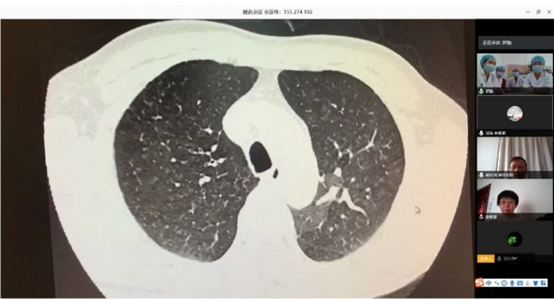

阜外医院肺血管病房充分利用“互联网+医疗”的优势作用 开展远程线上查房

2020-11-11